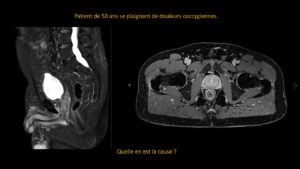

Deux mois après une entorse, persistance d’une importante douleur à la marche.

A droite pour comparaison, une radiographie de cheville qui est normale.

A gauche, le cheville du patient…quel est votre diagnostic?

Sur la radiographie simple, il est très difficile de visualiser la problématique.

La persistance de la douleur impose de réaliser une IRM qui révèle alors une fracture du calcanéum.